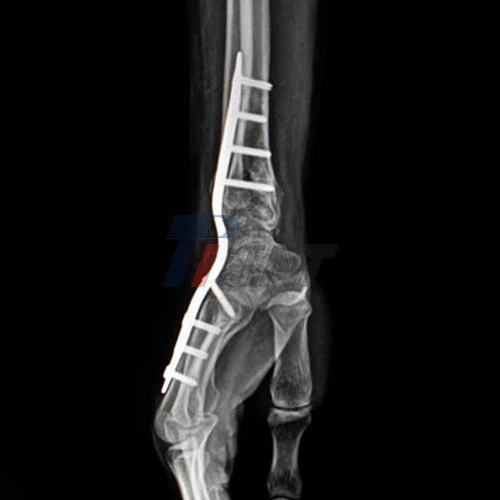

One of the most effective surgical techniques for treating wrist fractures is internal fixation using a titanium plate. This method involves placing a specially designed titanium plate across the fracture site and securing it with screws to hold the bone fragments in their correct position during the healing process.

Titanium plates provide superior stability to the fractured bone, allowing for better alignment and reduced risk of displacement during the healing process. This enhanced stability is particularly crucial for complex or comminuted fractures where multiple bone fragments need to be held in place. The rigidity of the titanium plate ensures that the wrist remains properly aligned, even when subjected to minor stresses or movements.

Titanium plate for wrist fracture is known for their exceptional strength-to-weight ratio and resistance to corrosion. These properties ensure that the fixation remains stable and effective over time, even when subjected to the stresses of daily activities. The durability of titanium plates also means that they can often be left in place permanently without causing issues, eliminating the need for a second surgery to remove the hardware.